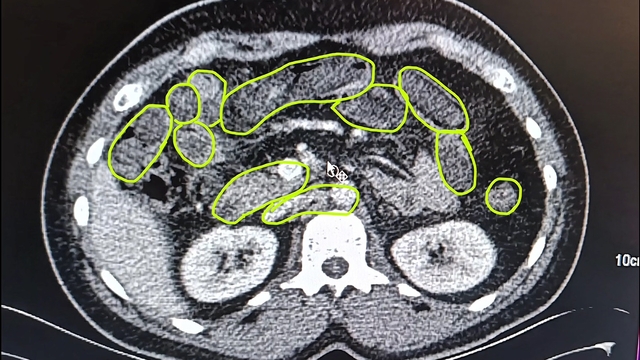

İl Jandarma Komutanlığı ekipleri, İran uyruklu A.O. (51), M.S. (37) ve P.S..'nin (28) ülkelerinden kente uyuşturucu getireceği bilgisine ulaştı. Şüpheliler Kocasinan ilçesi Himmetdede Mahallesi'nde taksi ile kente girmek istediği sırada durduruldu. Araçta yapılan aramada 15 gram esrar, 5 gram bonzai ve 117 adet uyuşturucu hap ele geçirildi. Gözaltına alınan 3 şüpheli muayene olmak üzere Kayseri Şehir Hastanesi'ne getirildi. Röntgen ve ultrason sonrası kontrollerde 3 şüphelinin midesinde uyuşturucu madde olduğu belirlendi. Şüphelilerin yuttukları uyuşturucuları kente sokmaya çalıştıkları tespit edildi. Kapsüller, sağlık ekibinin müdahalesiyle çıkarıldı. Taburcu edilen şüpheliler, İlçe Jandarma Komutanlığı'na götürüldü.